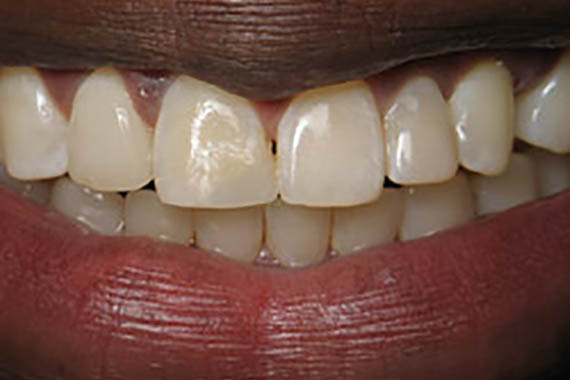

Crowns

Before

After